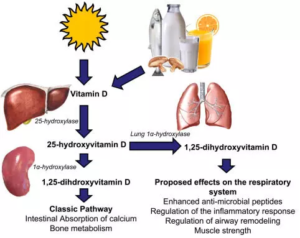

Vitamin D Deficiency tied to increased Respiratory Infection Risk in Preschool Children: Study

Researchers have found in a new study that vitamin D deficiency…